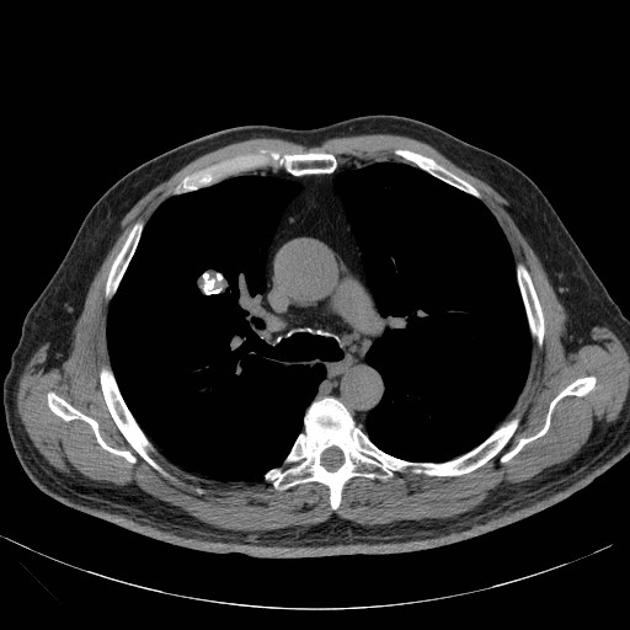

・solid nodule(充実結節)

・pure ground-glass nodule(pure GGN:いわゆるスリガラス影)

・part-solid nodule(狭義の部分充実結節)